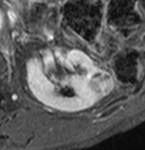

[画像診断]脳腱黄色腫症のMRI 2010-04-14